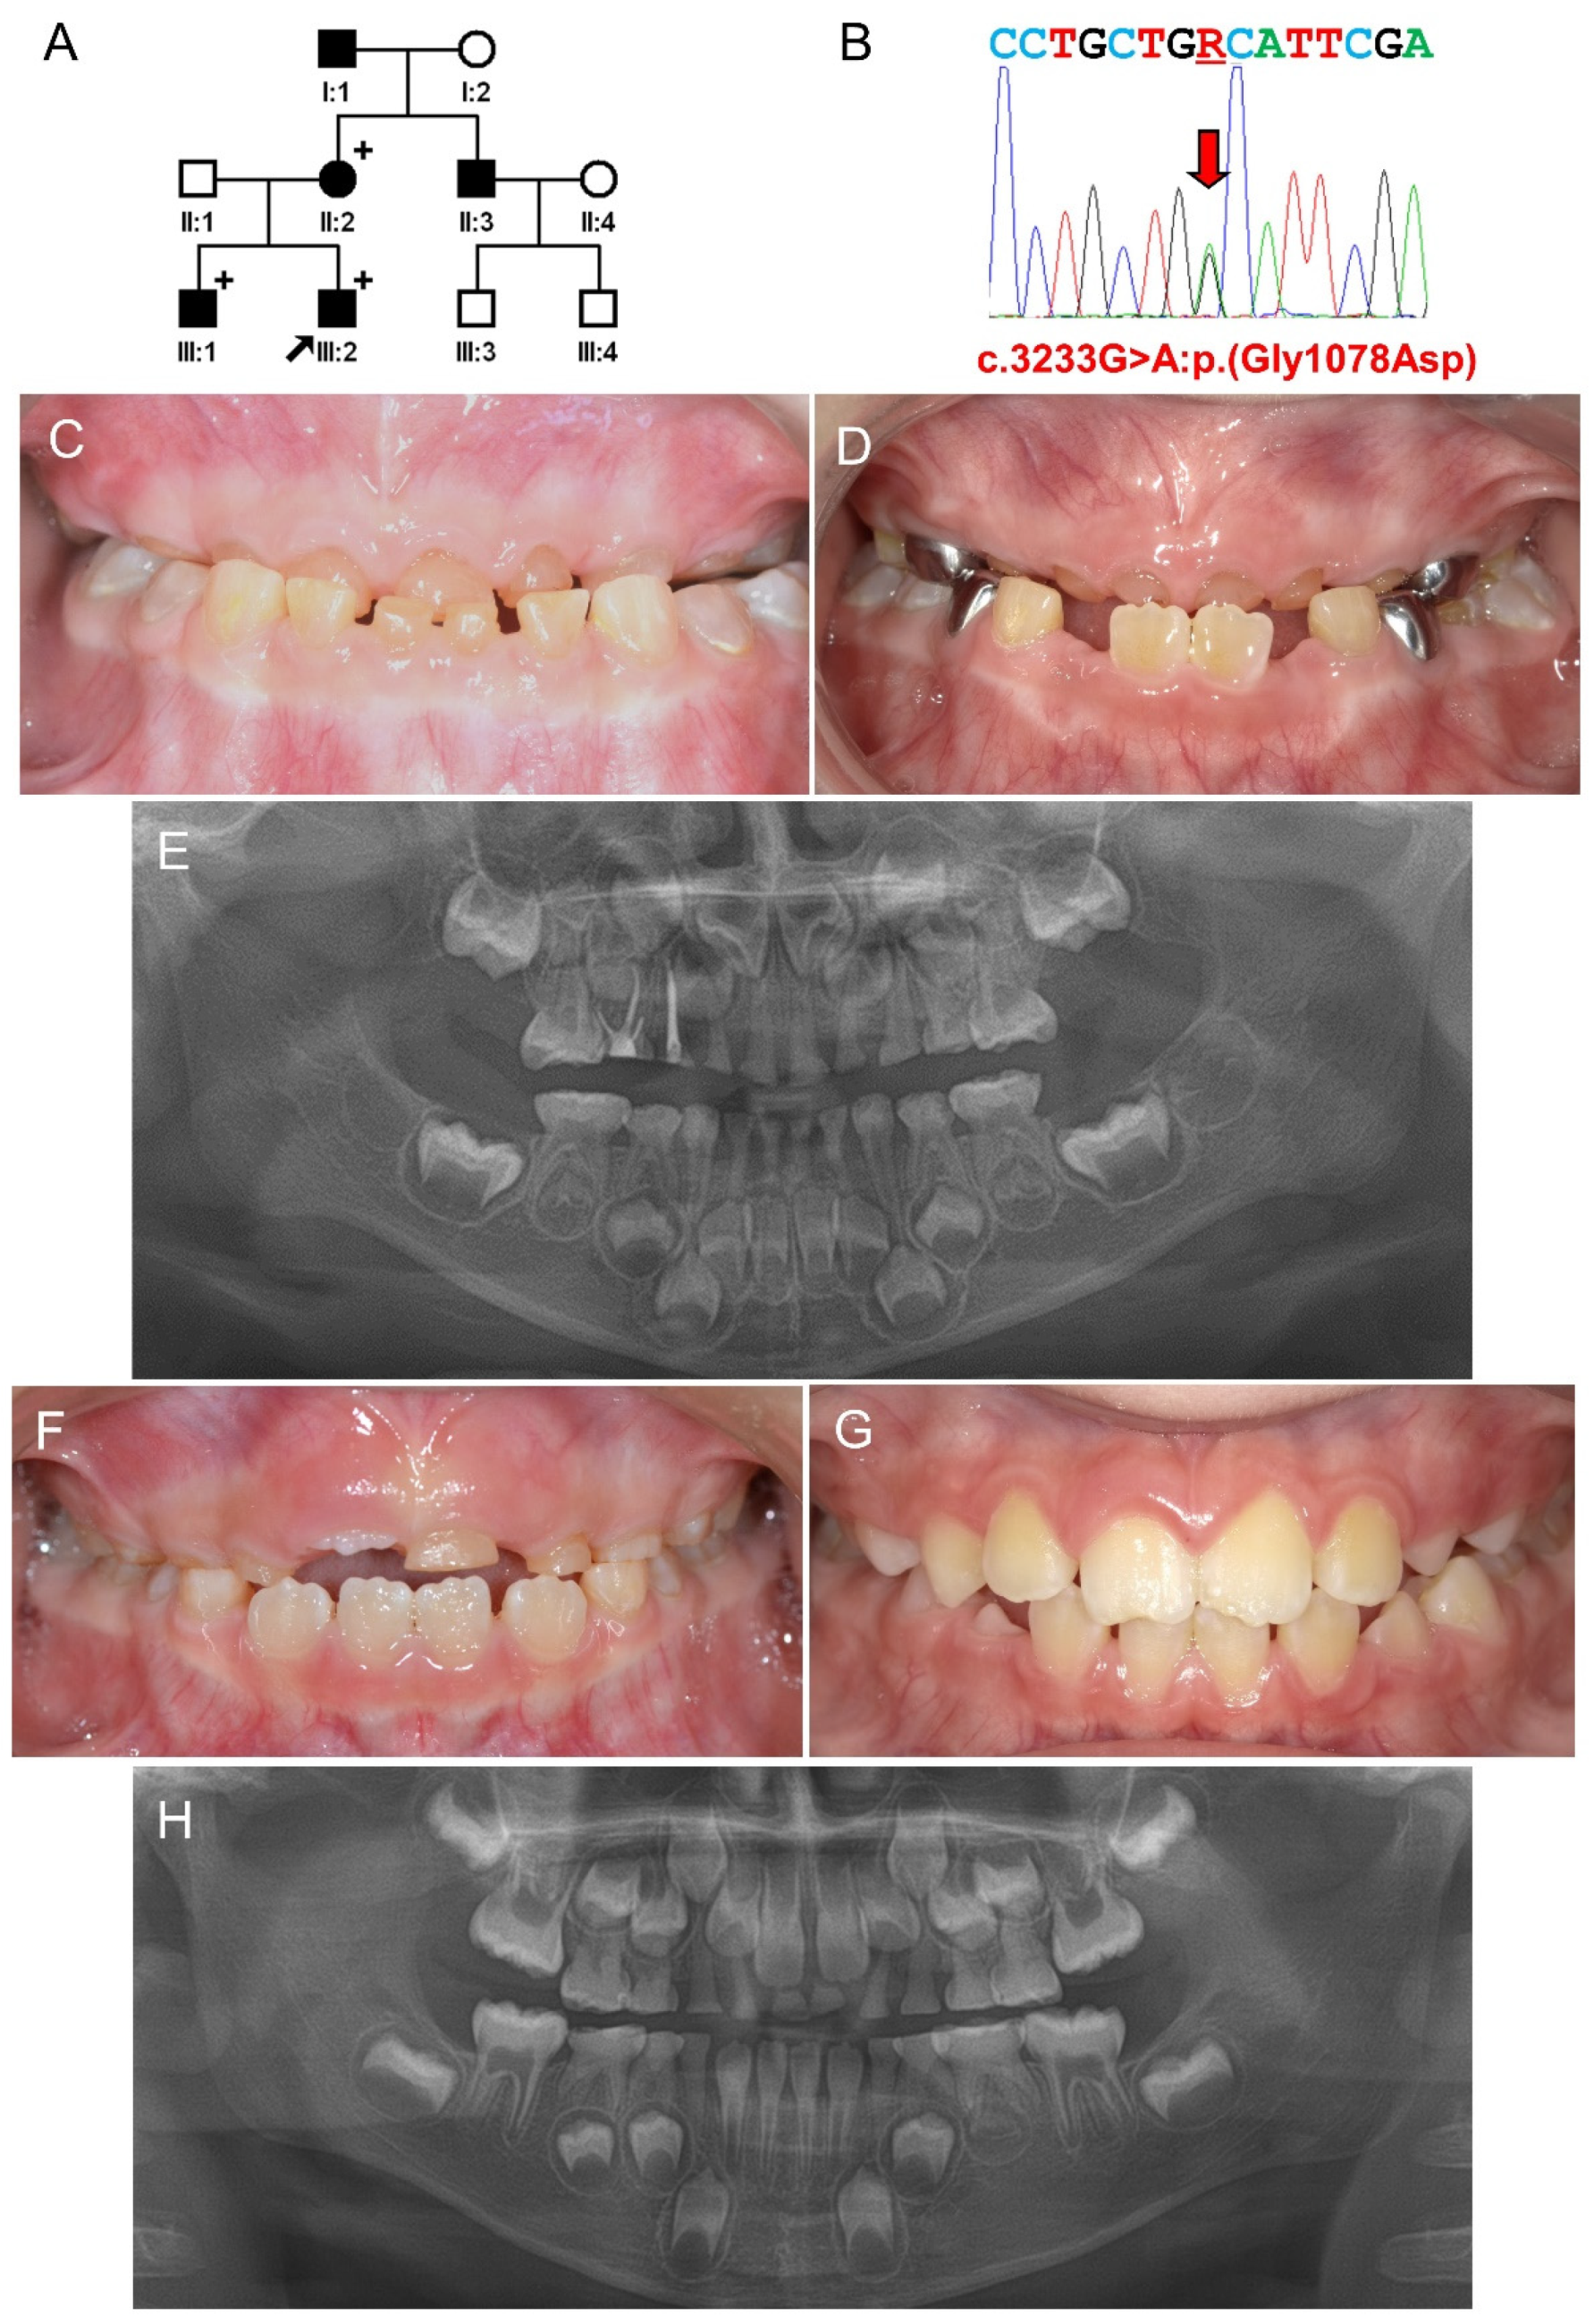

3.1. Family 1